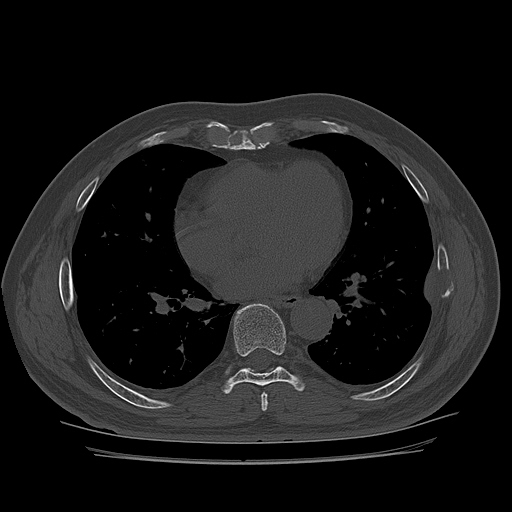

CT ; metastacic mass at rib and adjacent lung

CT image